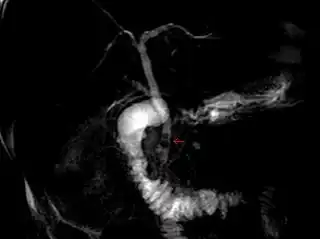

![]() Cálculos impactados en el conducto biliar común (flecha roja). | ||